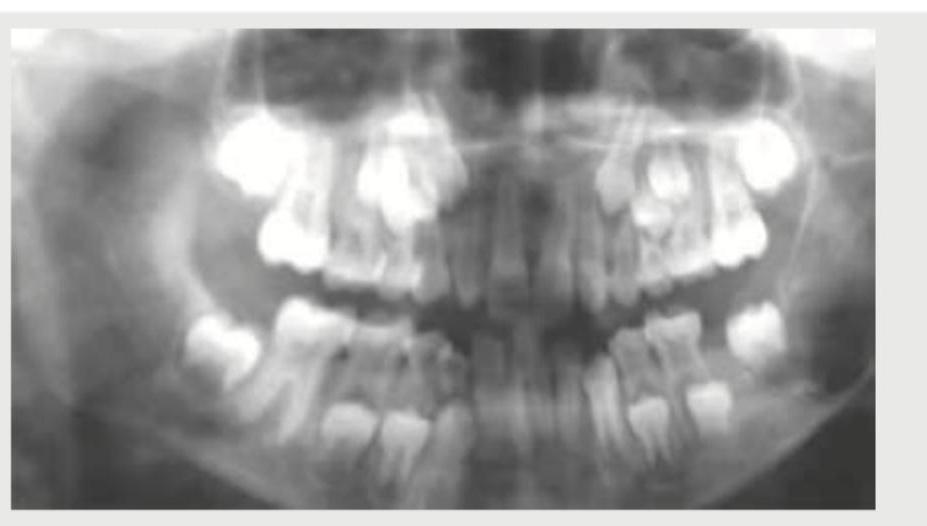

The following image shows:

Explanation: ***Orthopantomogram*** - The image displays a panoramic view of the upper and lower jaws, including all teeth, the temporomandibular joints, and surrounding bone structures, which is characteristic of an **Orthopantomogram (OPG)** or panoramic radiograph. - This type of radiograph is commonly used in dentistry to assess the overall dental status, detect **impacted teeth**, and evaluate **bone pathology** across the entire oral cavity. *Water's view* - A **Water's view** (occipitomental view) is a radiographic projection typically used to visualize the maxilla, sinuses (especially the maxillary sinuses), and orbits. - It does not provide a panoramic view of the entire dental arches as seen in the image. *Invertogram* - An **invertogram** is a specialized lateral radiographic view of the abdomen and pelvis, particularly positioned to show the anus and rectum. - It is primarily used to assess **anorectal malformations** in infants and has no relation to dental imaging. *Gynogram* - The term **gynogram** is not a standard or recognized medical imaging technique. - Imaging studies related to gynecological conditions typically involve ultrasound, MRI, or CT scans of the pelvis, not a specific "gynogram" X-ray.